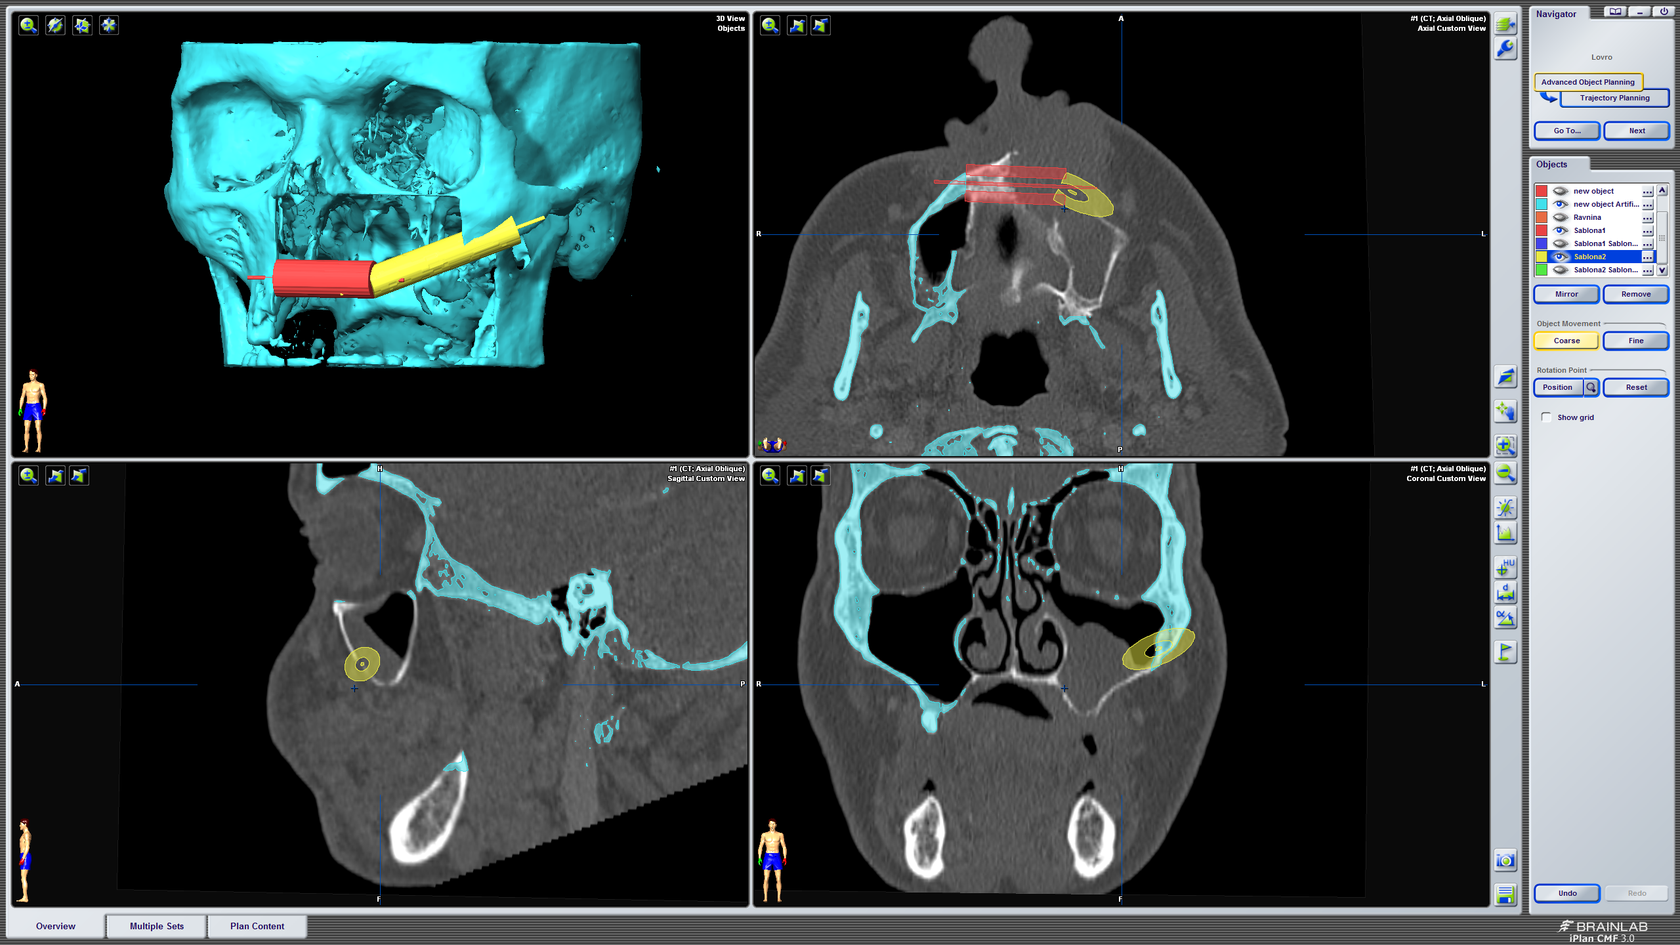

Kompjutorsko planiranje i simulacija

3D kompjutorsko planiranje rekonstrukcije defekta gornje čeljusti